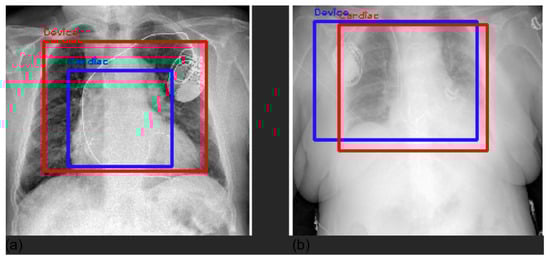

3.4. Grad-CAM